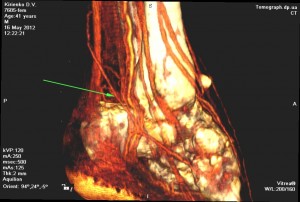

Послеоперационный период протекал гладко, без каких либо осложнений. Оба лоскута прижили в реципиентных зонах, обеспечив тем самым восстановление кожного покрова, утраченного объема мягких тканей, покровной, каркасной, кинематической и эстетической функций (Рис 3). Кроме того, наличие постоянного артериального кровоснабжения этих лоскутов обеспечило устойчивое улучшение кровообращения или реваскуляризацию скальпированных и поврежденных костных структур стопы за счет включения в состав лоскутов двух артерий: суральной и кожной перфорантной ветви от малоберцовой артерии. Последние хорошо визуализируются на КТ- ангиографическом исследовании с 3-D моделированием (Рис 4).

Рис. 4. Вид распределения сосудистой сети левой стопы после операции на КТ- ангиографическом исследовании с 3-D моделированием; Слева – со стороны медиальной поверхности, где рана закрыты «суральным» лоскутом с дистальным основанием определяется a. suralis (стрелка) в проекции питающей ножки лоскута; Справа – со стороны тыльно-латеральной поверхности, где рана закрыта латеральным надлодыжечным лоскутом определяется перфорантная ветвь – ramus cutaneous от a. fibularis (стрелка) в проекции питающей ножки лоскута.